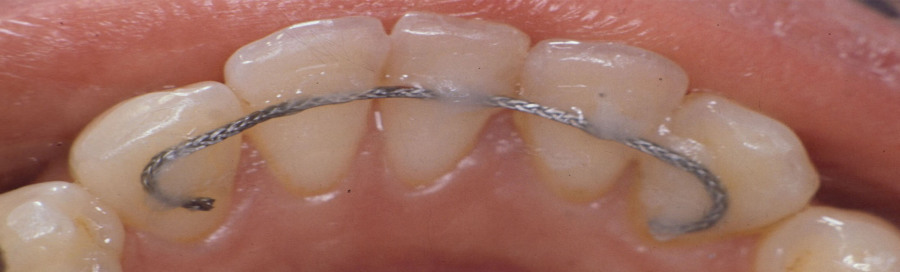

Geklebte Retainer zur Langzeitstabilisierung bieten einen effektiven Schutz gegen das Verschieben von Schneidezähnen und sorgen dafür, dass gerade Zähne auch gerade bleiben.